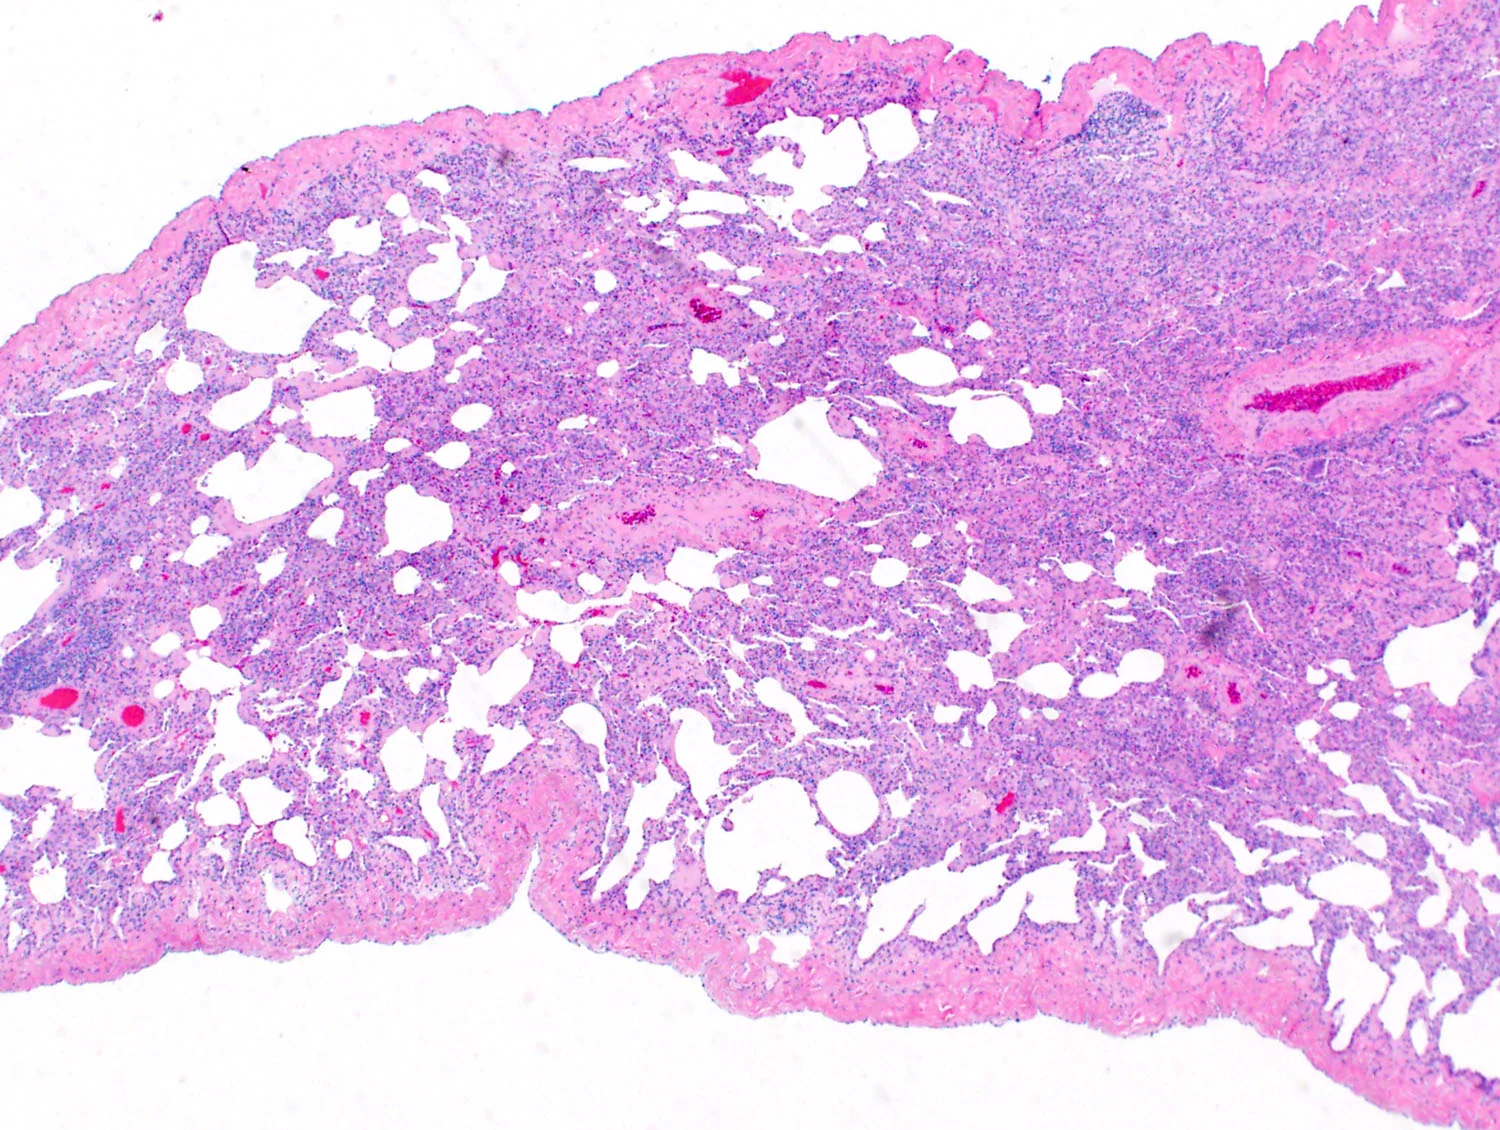

Cellular Infiltrates Sub-Patterns

There are 7 sub-patterns in the setting of cellular infiltrates.

Choose the image most similar to your case. A differential diagnosis is given below.

Cellular interstitial pneumonia (see comment).

Comment: The biopsy shows extensive cellular interstitial infiltrates. No additional specific histologic features to indicate an etiology are identified. There is a broad differential diagnosis including subacute HP, cellular NSIP, CTD, infection, alveolar hemorrhage, drug reaction, aspiration, lymphoproliferative disease (including LIP), and as an idopathic entity. The diagnosis of ILD requires a multidisciplinary approach. Correlation with imaging studies, serology, microbiology studies, and clinical history is suggested.